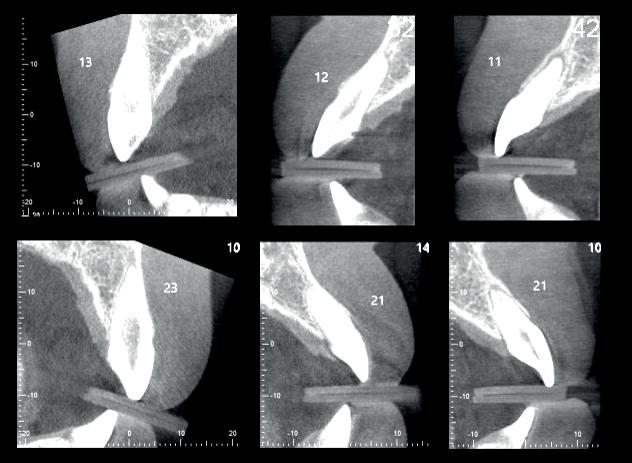

Bij een 15-jarige gezonde jongen werd tijdens een caféruzie op zondagnacht een stoel tegen zijn gezicht gegooid. Hierbij was sprake van flink dentaal trauma:

• De 13 was geavulseerd.

• De 12 en de 11 waren naar palatinaal geluxeerd.

• In het onderfront waren kroonfracturen zichtbaar in de 42, 41 en 31.

Na de avulsie is de 13 bij de afdeling kaakchirurgie in een oplossing van fysiologisch zout bewaard (onbekend hoe lang na het trauma) en na ongeveer zes uur post-trauma onder anesthesie in de alveole teruggeplaatst. Toen zijn ook de 12 en de 11 gereponeerd en is er een staaldraadspalk aangebracht van de 14 naar de 22. Tevens is de lip gehecht. Er is niets aan de afgebroken ondertanden gedaan, maar dringend geadviseerd deze zo snel mogelijk te laten afdekken door de eigen tandarts.

Na zes weken zagen wij hem voor het eerst bij ons in de praktijk voor consult. Hij was klachtenvrij en kon redelijk kauwen met zijn tanden (afbeelding 1-6).

Diagnose

Symptomatische parodontitis apicalis met externe resorptie 13 t.g.v. infectie.

• Onduidelijk voor de 12 en de 11, mogelijk nietpijnlijke parodontitis apicalis 11 t.g.v. infectie.

• Symptomatische pulpitis 42, 41 en 31, onduidelijk of reversibel of niet.

Therapie

• Zo snel mogelijk spalk verwijderen en endodontische behandeling 13.

• Proefboren 12 en 11 en indien nodig endodontische behandeling. Tijdelijke restauraties 42/41/31 verwijderen en opbouwen en, indien nodig, endodontische behandeling.

Behandeling 13, 12, 11

We zijn begonnen met de 13 en hebben een week later de 12 en de 11 behandeld. Bij de 13 kon een volledig necrotische pulpa worden geëxtirpeerd (afbeelding 7). Aangezien we aan de vitaliteit van de 12 en 11 twijfelden, hebben we eerst een proefboring uitgevoerd en beide elementen bleken volledig necrotisch.

De kanalen zijn ultrasoon gespoeld met 2% NaOCl en EDTA onder isolatie van rubberdam. Het kanaal van de 13 is gevuld met MTA (afbeelding 8), omdat er sprake was van een niet-afgevormde radix. Dit is afgedekt met een laagje Vitrebond. In de 12 en 11 hebben we guttapercha en AH26 aangebracht via een hybride vultechniek (afbeelding 9).

Er is een plastische opbouw vervaardigd van het composiet opbouwmateriaal Clearfil core, dat diep is verankerd in het kanaal. Er is een definitieve restauratie vervaardigd van composietmateriaal Filtek Z250 kleur A3 (afbeelding 10 en 11). De behandeling is technisch goed verlopen. Echter, we hebben hem en zijn moeder uitgelegd dat de prognose

van de 13 voor de lange termijn dubieus was.

Behandeling 42, 41, 31

Na het verwijderen van de lekkende glasionomeerspalk, lagen alle pulpae bloot. De 42 was bovendien verticaal gefractureerd (afbeelding 12 en 13). Het topje van de pulpae van de 31 en 41 kon worden verwijderd, en na spoelen met NaOCl persisteerden twee vitale pulpae, die zijn afgedekt met een laagje Vitrebond (afbeelding 14).